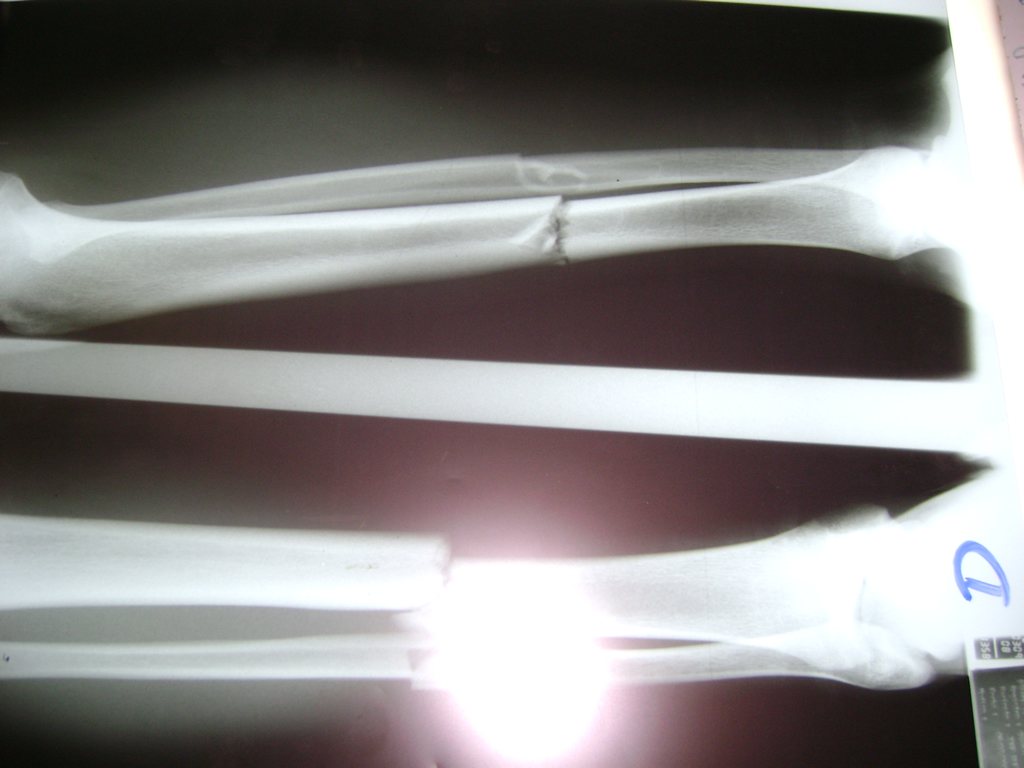

La mayor parte de las roturas implican a la parte proximal del hueso (parte del hueso próximo a la rodilla) o a la parte distal (parte del hueso cerca del tobillo).

Debido a la fina cobertura de piel que recubre la tibia y el peroné, las fracturas generalmente son abiertas, es decir, el hueso roto rasga la piel, atravesándola. Las fracturas de tibia y peroné generalmente se producen por un fuerte impacto o torsión.